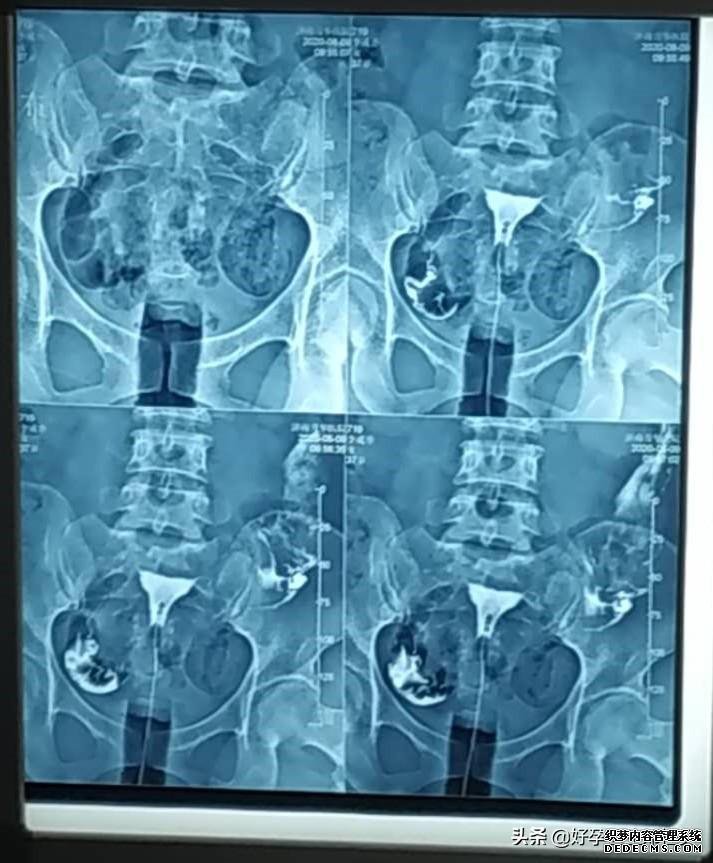

输卵管复查后,我开始教李姐怎么测排卵算准排卵日安排同房,把受孕几率提到最高,这样才坚持了三个月,李姐就如愿怀孕了,昨天去查了血(查血报告见上方图一,下面是试纸图),各方面值都非常好,这下李姐总算是放心了!

子宫输卵管造影是通过导管向子宫和输卵管注入造影剂,通过X线来透视和摄片,然后根据造影剂在输卵管和盆腔内的造影情况分析输卵管通畅程度、阻塞的部位和宫腔的情况,是临床上很多不孕症女性常做的检查之一。